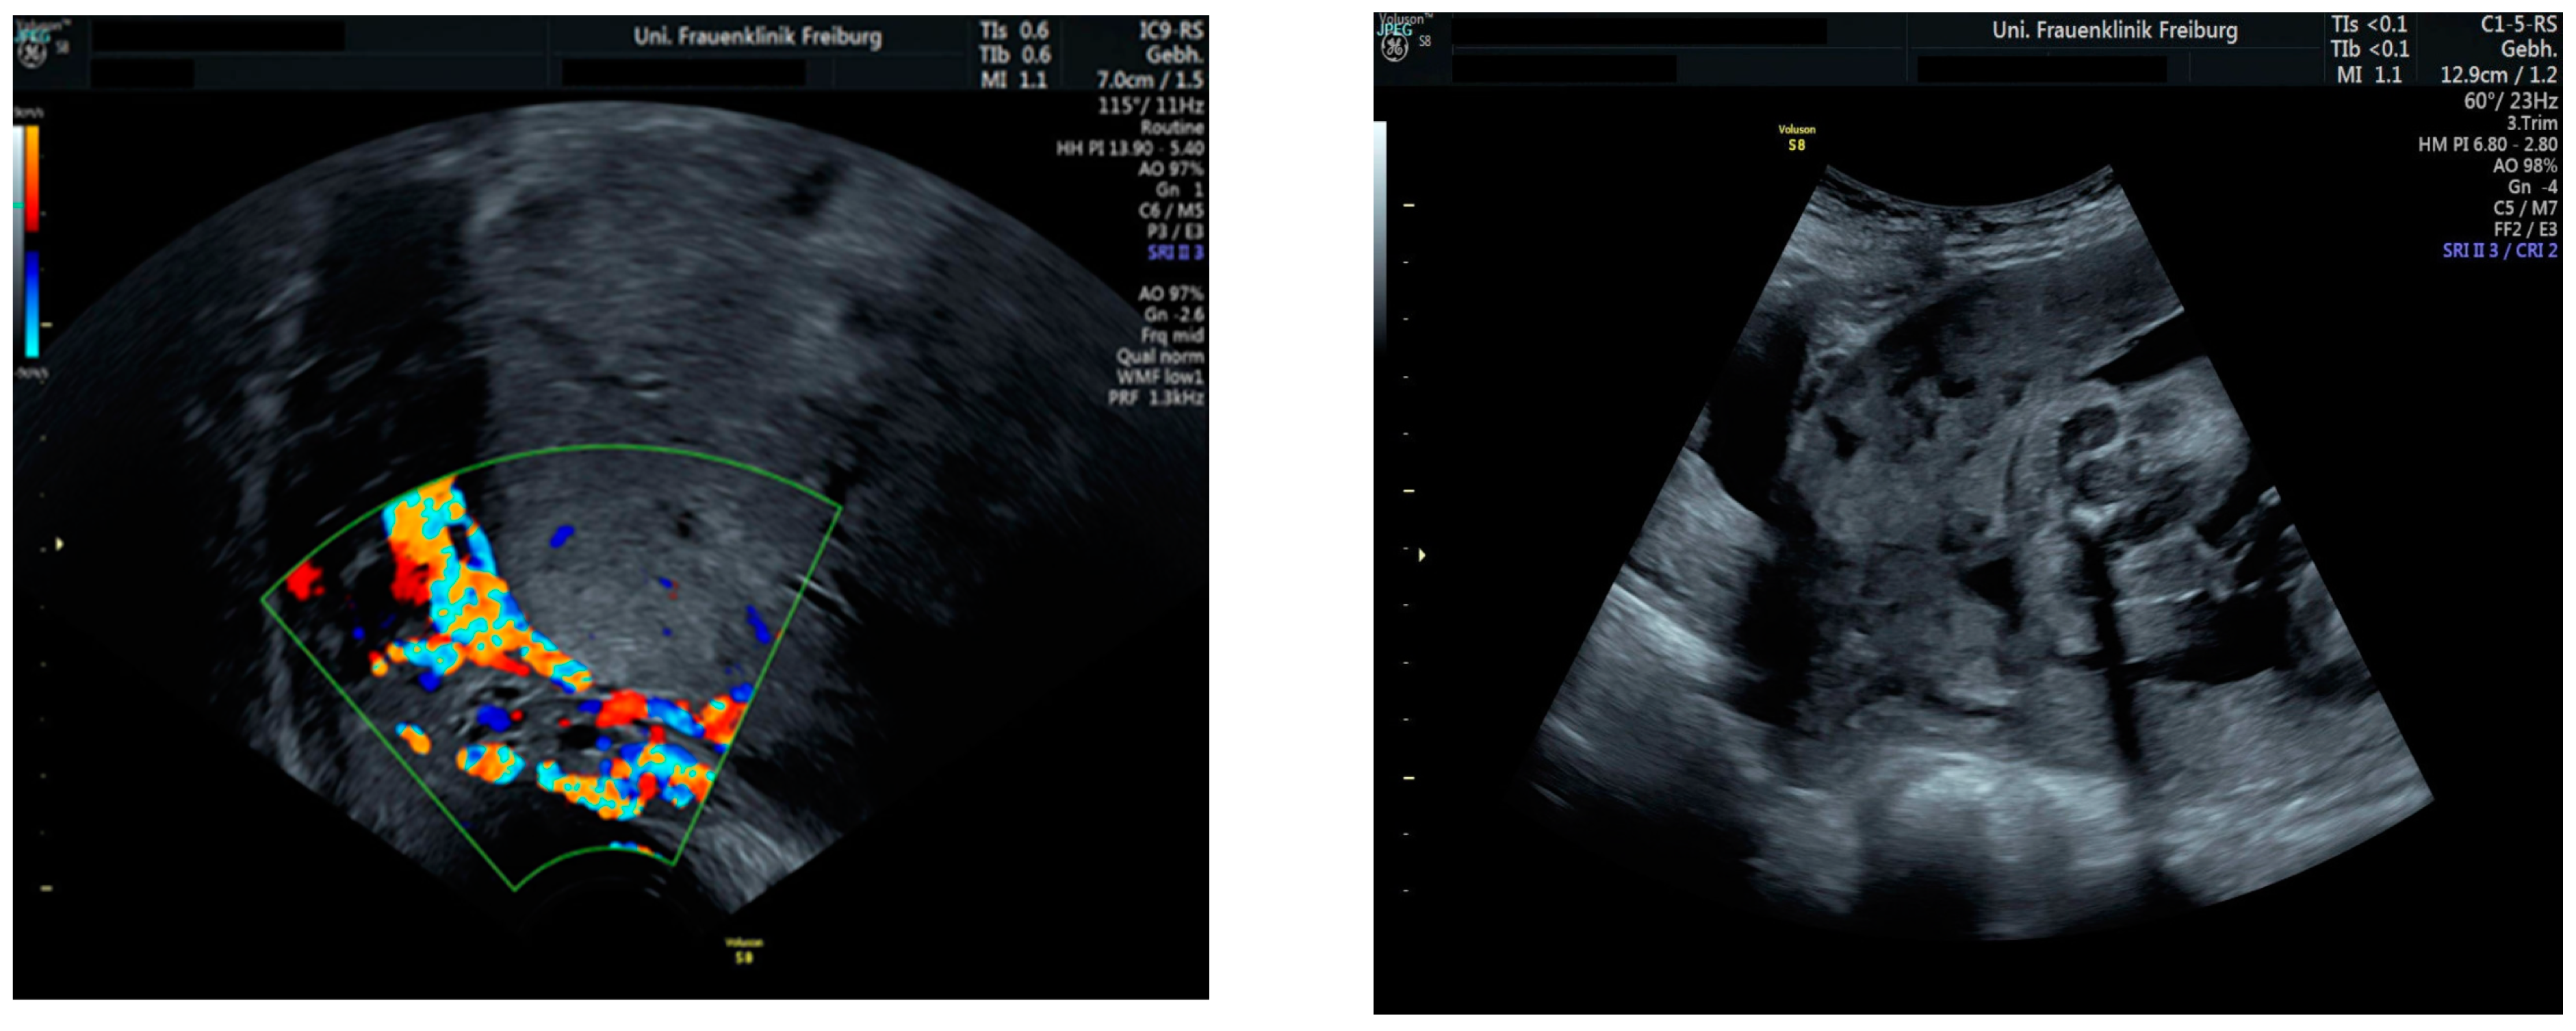

Sonographic findings (Figure 11):

Figure 11.

Increased placental blood flow on 2D ultrasound. Red color represents increased placental blood flow moving to the transducer; blue color represents placental blood flow moving leaving away from the transducer.